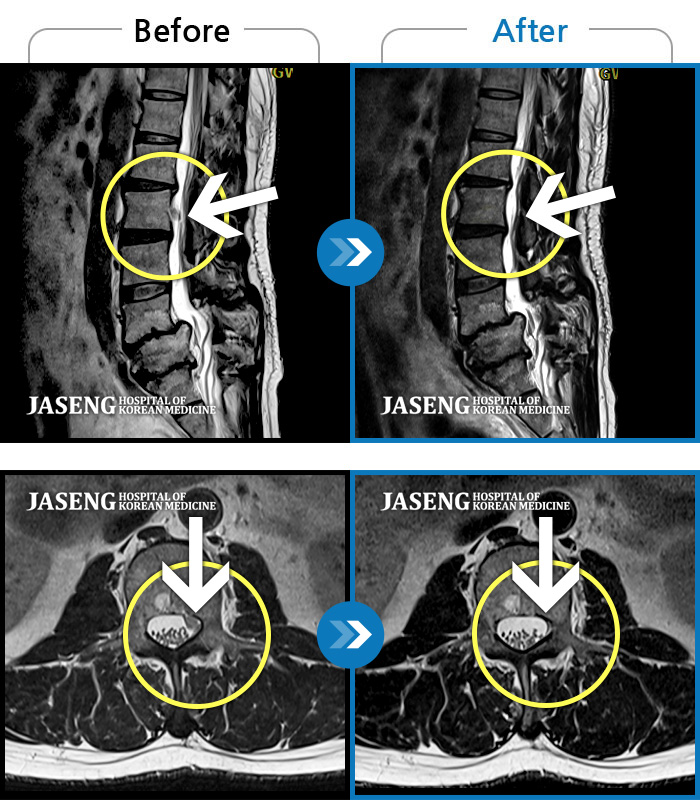

허리디스크

광주 · 장영우 원장

허리 양측부터 골반까지 통증, 우측 하지 외측으로 이어지는 저린감

촬영시기

2020.11.12 ~ 2021.10.18

2021.10.22